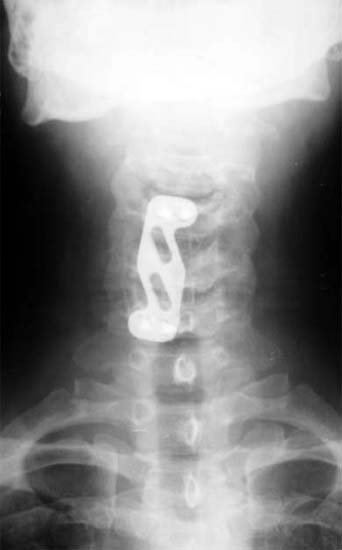

颈椎5骨折,椎体及间盘压迫硬膜囊,患者高位截瘫

前路减压,椎间植骨,钢板内固定,同期进行后路减压手术。 截瘫部分恢复,生活自理。